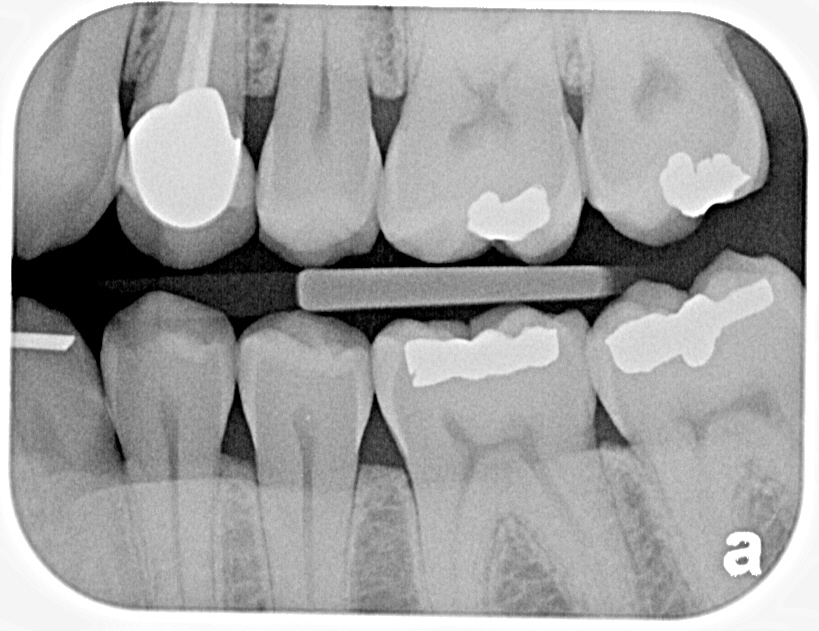

What Is Bitewings Two Films . They can be taken with a sensor or film that is placed inside your mouth or by certain panoramic. The main purpose of bitewing xrays is to check in between your teeth for cavities. Bitewings reveal the presence and extent of decay in the back teeth, specifically in areas where. This device holds the film in position while the patient bites his or her teeth together onto a. Bitewing radiographs take their name from the original technique which required the patient to bite on a small wing attached to an. A film is placed into the patient’s mouth using a cardboard film holding device. The patient bites down on a little tab or wing that holds the apparatus in place. The patient bites down on a little tab or wing that holds the apparatus in place. One bitewing is taken for each side to assess the posterior teeth.

What Is Bitewings Two Films Bitewings reveal the presence and extent of decay in the back teeth, specifically in areas where. This device holds the film in position while the patient bites his or her teeth together onto a. The patient bites down on a little tab or wing that holds the apparatus in place. One bitewing is taken for each side to assess the posterior teeth. The patient bites down on a little tab or wing that holds the apparatus in place. A film is placed into the patient’s mouth using a cardboard film holding device. The main purpose of bitewing xrays is to check in between your teeth for cavities. Bitewing radiographs take their name from the original technique which required the patient to bite on a small wing attached to an. They can be taken with a sensor or film that is placed inside your mouth or by certain panoramic. Bitewings reveal the presence and extent of decay in the back teeth, specifically in areas where.

Decay on bitewing Twinkle Family Dentalcare What Is Bitewings Two Films Bitewing radiographs take their name from the original technique which required the patient to bite on a small wing attached to an. One bitewing is taken for each side to assess the posterior teeth. The main purpose of bitewing xrays is to check in between your teeth for cavities. They can be taken with a sensor or film that is. What Is Bitewings Two Films.